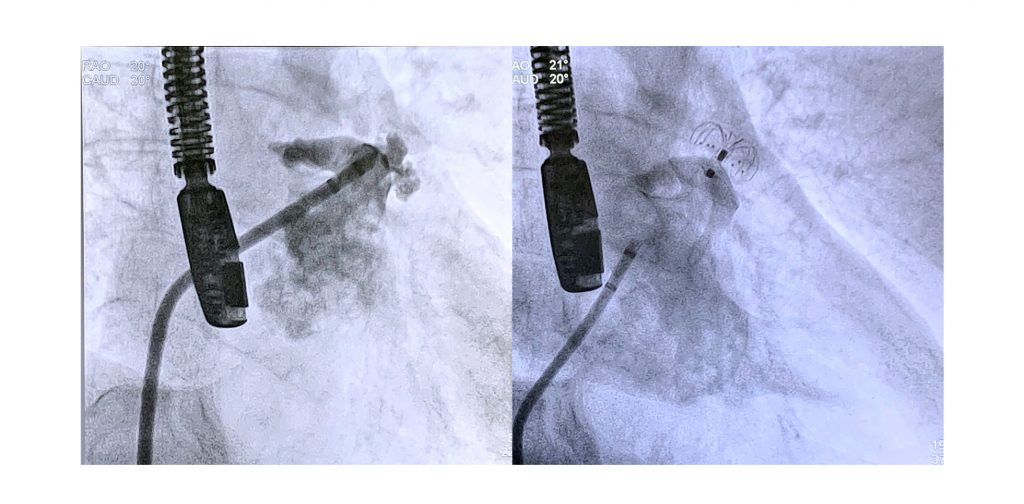

Descrever os primeiros resultados de uma experiência inicial multicêntrica no Brasil e investigar a viabilidade, a segurança e a eficácia da oclusão do AAE com o novo dispositivo LAmbre.

Coletamos dados do procedimento e do acompanhamento de 51 pacientes consecutivos com FANV, restrições para ACO em longo prazo e com anatomia adequada, submetidos à oclusão do AAE com o dispositivo LAmbre em 18 centros no Brasil. Indicações para o procedimento foram: sangramento importante em pacientes recebendo ACO (47,1%), AVC ou trombo persistente no AAE apesar de ACO adequada (27.5%), sangramento e AVC (17.6%), outras contraindicações clínicas apara ACO (5,9%), e escolha do paciente devido à prática esportiva (1,9%).

Foram estudados 25 homens (49%) e 26 mulheres (51%), com idade média de 76±7,7 anos, escore CHA2DS2-VASc médio de 4,6± 1,7 e escore HAS-BLED médio de 3.4± 1,1. A taxa de sucesso do procedimento foi de 100%. As complicações imediatas relacionadas ao procedimento foram derrame pericárdico em dois pacientes, e embolização do dispositivo em um caso. Não foram observados shunts residuais > 5mm. Shunts < 5mm foram detectados em quatro pacientes por Doppler colorido ao final do procedimento. Após um período médio de acompanhamento de 18 meses ± 12 meses, não foram observados óbito, AVC ou complicações maiores.